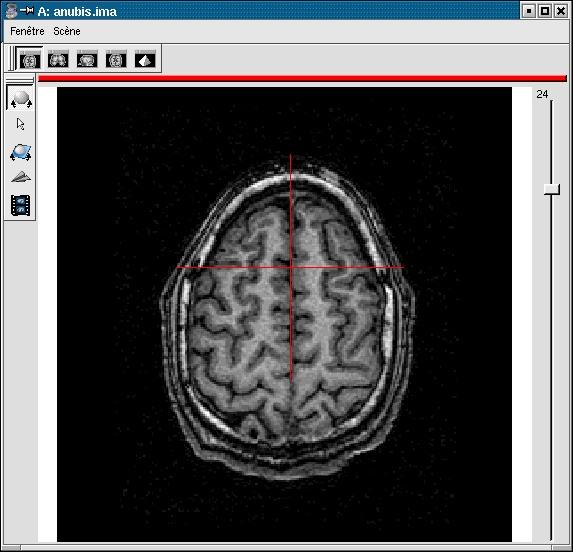

If your image is not spatially normalised, Anatomist will help you to click on the 3 or 4 points of interest.

- If the volume is not already visible, click on the edit button of one of the point parameters to have Anatomist display it

- Set the Anatomist view so as to see the point (use the slice slider) and click in it on the wished point.

- When the cursor position is good, click on the button of the 3D point in BrainVISA: the position is transfered from Anatomist to BrainVISA.

- If you are not happy with the position, you can restart the operation: click again on other points then on the parameter button to validate: a new position replaces the previous one in BrainVisa.

You have to select 3 points (you can use a sagittal slice if you prefer):

- Intersection of anterior commissure with interhemispheric plane;

- Intersection of posterior commissure with interhemispheric plane;

- Any point of the interhemispheric plane not aligned with the previous ones.

- Optionally, any point of the left hemisphere. Specifying this point is not mandatory, it is only useful to detect a possible orientation problem on the input image. Be careful, axial and coronal views in Anatomist are in radiological convention by default (left and right are flipped).

Anterior commissure: